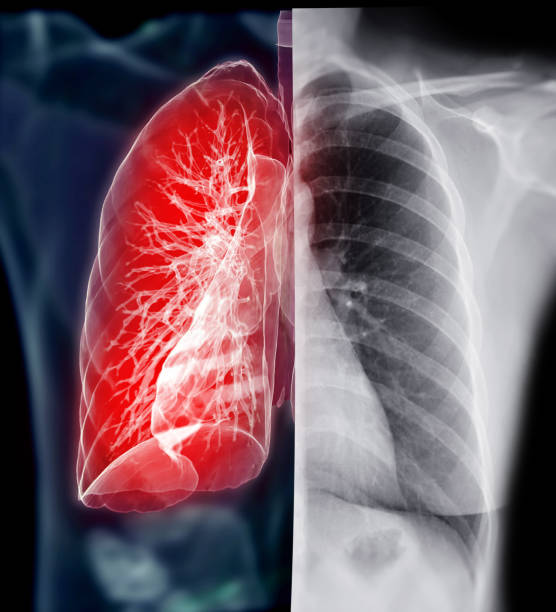

천식

천식은 기관지의 염증과 경련으로 인해 기침, 숨이 차고 가슴이 답답한 등의 호흡곤란 증상을 보이는 만성적인 폐질환입니다. 이러한 천식 환자들은 종종 목이 간질간질하고 마른 기침이 나타날 수 있습니다.

천식의 원인은 다양하지만, 대개는 호흡기에 접촉한 알레르기성 물질이나 공기 오염 물질에 대한 반응으로 인한 것입니다. 이러한 반응으로 인해 호흡기의 기관지가 수축하고 염증이 생겨 호흡 곤란 증상이 나타납니다. 이때, 기침은 호흡기를 청소하고 비염, 기관지염 등으로 인한 분비물을 제거하는 역할을 합니다.

하지만, 천식 환자의 경우 호흡기의 염증과 경련으로 인해 기침이 잘 제어되지 않아 목이 간질간질하고 마른 기침이 나타나게 됩니다. 또한, 천식 환자는 호흡 곤란으로 인해 호흡을 하려고 할 때 공기가 막혀 기침을 유발할 수 있습니다. 따라서, 천식 환자가 목이 간질간질하고 마른 기침이 나타날 경우 즉각적인 치료가 필요합니다. 천식은 약물 치료와 호흡 운동 치료 등으로 적극적으로 치료가 가능하며, 적절한 치료로 호흡기 증상을 완화시킬 수 있습니다.